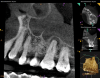

As part of the endodontic evaluation, CBCT imaging showed periapical pathology associated with tooth No. 14 as well as significant MSEO (Figure 7 and Figure 8). Clinical testing confirmed the absence of a cold response but no tenderness to percussion or palpation. A composite buildup was in place, absent evidence of recurrent decay. Soft tissues were unremarkable.

Fig 7 and Fig 8. Preoperative CBCT scans showing evidence of periapical pathology on tooth No. 14 as well as communication with the adjacent maxillary sinus and associated mucositis. Fig 7: Sagittal view, buccal roots No. 14. Fig 8: Sagittal view, palatal root No. 14.

Figure 7

Fig 8. Preoperative CBCT scans showing evidence of periapical pathology on tooth No. 14 as well as communication with the adjacent maxillary sinus and associated mucositis. Fig 7: Sagittal view, buccal roots No. 14. Fig 8: Sagittal view, palatal root No. 14.

Figure 8